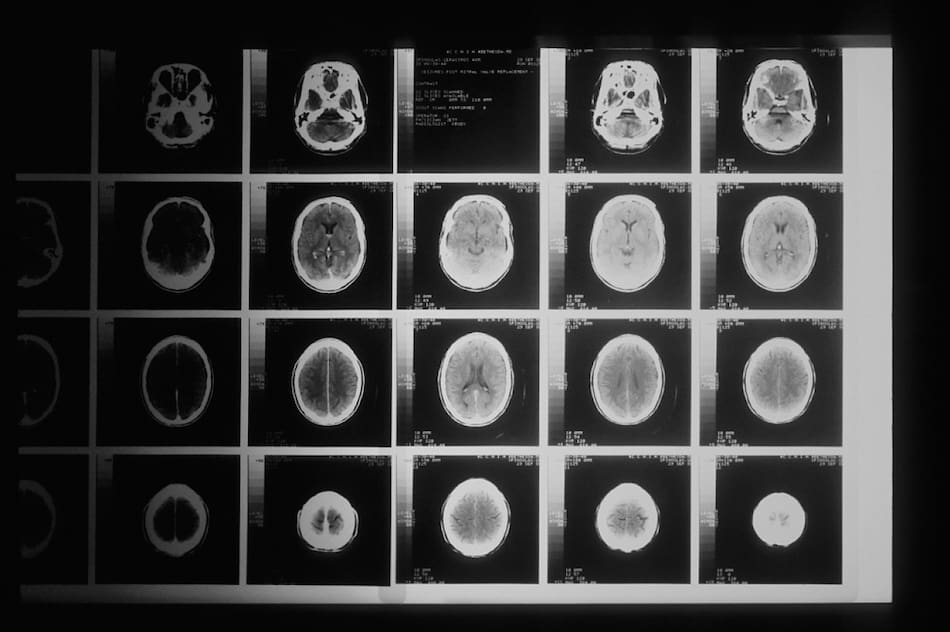

El glioblastoma es un tumor maligno que afecta al cerebro. Para la mayoría de las personas, la expectativa de vida promedio después del diagnóstico es de entre 12 y 15 meses. Sin embargo, investigadores de la Universidad de Florida se encuentran trabajando en una vacuna contra esta letal enfermedad.

El glioblastoma es un tipo de cáncer que afecta al cerebro. Foto: Unsplash.